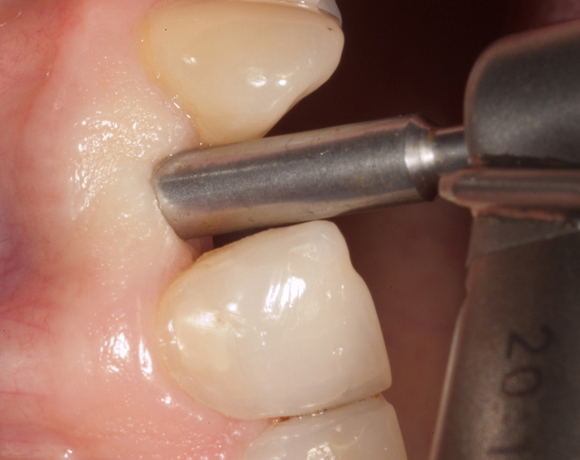

Im vorliegenden Patientenfall musste der Zahn 22 nach erfolgloser Endodontie entfernt werden. Die Nachbarzähne waren kariesfrei, es wurde eine Marylandbrücke (eine Brücke mit zwei Flügelchen, die palatinal an den Nachbarzähnen verklebt werden) oder ein Implantat besprochen. Die Patientin hat sich für ein Vollkeramikimplantat entschieden. In der Diashow wird der operative Eingriff bis zur fertigen Krone gezeigt. Die Einheilzeit betrug drei Monate.